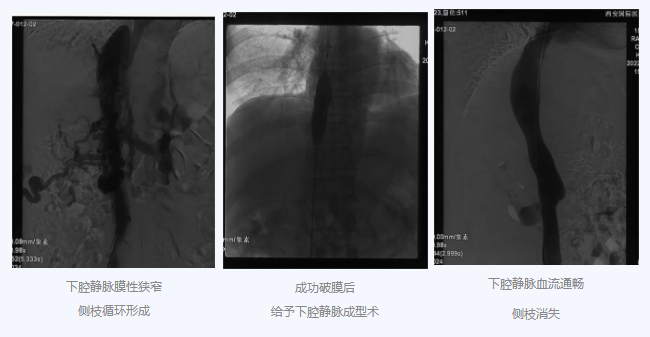

入院后,在韓國宏院長的安排下,臨床經(jīng)驗(yàn)豐富的醫(yī)師給老謝做了B超、CT 等檢查,結(jié)果顯示:三支肝靜脈近心端閉塞,肝內(nèi)側(cè)枝循環(huán)形成,下腔靜脈近心房入口處隔膜樣狹窄,隨后的DSA血管造影也證實(shí):下腔靜脈狹窄,且有側(cè)枝形成,最終確診困擾老謝20年的疾病為混合型布加綜合征,是一種罕見病。

明確診斷后,韓院長帶領(lǐng)團(tuán)隊(duì)縝密分析老謝的病情,為其制定最佳的治療方案,考慮到老謝的根本病因是下腔靜脈阻塞,介入手術(shù)成為首選治療方法,通過微創(chuàng)介入手術(shù),可準(zhǔn)確打通患者的閉塞血管,癥狀迅速緩解。做好充分術(shù)前準(zhǔn)備后,為患者行“下腔靜脈成型術(shù)”,精準(zhǔn)定位快速貫通,閉塞的下腔靜脈順利開通,手術(shù)圓滿完成。